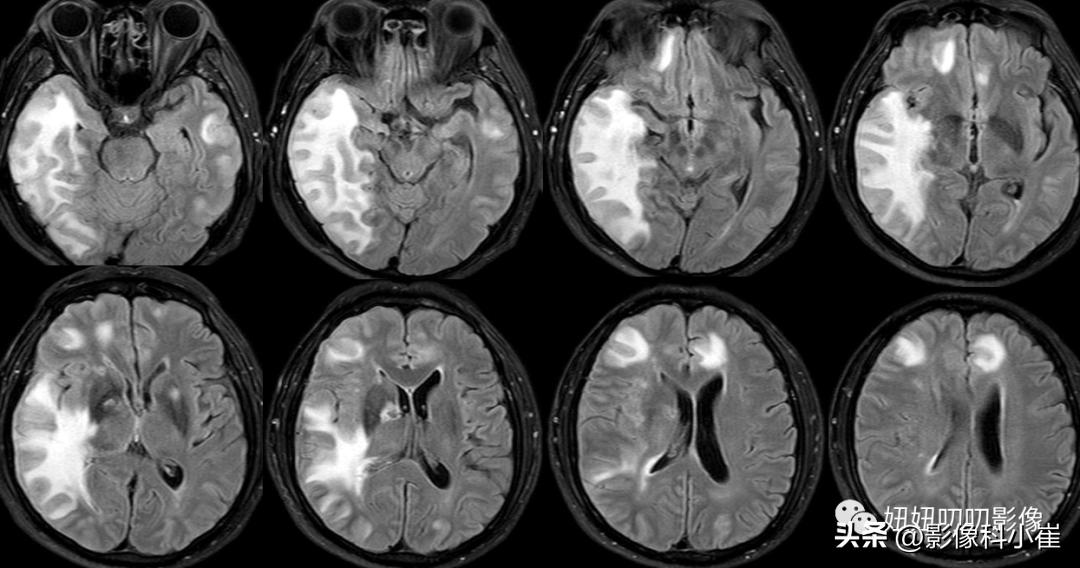

双侧基底节区、侧脑室周围白质、额顶叶皮层下见多发斑点状、斑片状等长 T1、长T2 异常信号灶,T2 Flair呈高信号,DWI及ADC示右侧基底节区病灶扩散受限。脑室系统形态未见明显扩张脑沟、脑裂未见明显增宽。中线结构未见明显移位。